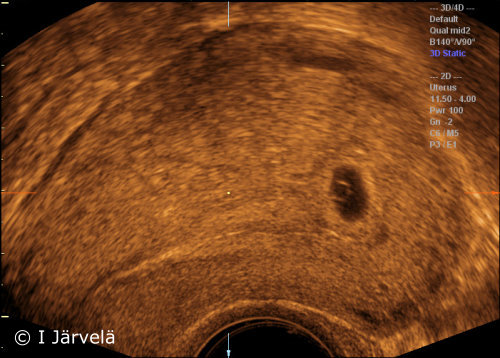

Pregnancy Week 5 (Ultrasound Scan)

Pregnancy week 5 (ultrasound scan). In the 5th week of pregnancy, a gestational sac (GS) containing a yolk sac (YS) can be seen in the uterus.

Picture: Ilkka Järvelä; text: Dimitrios Scordas